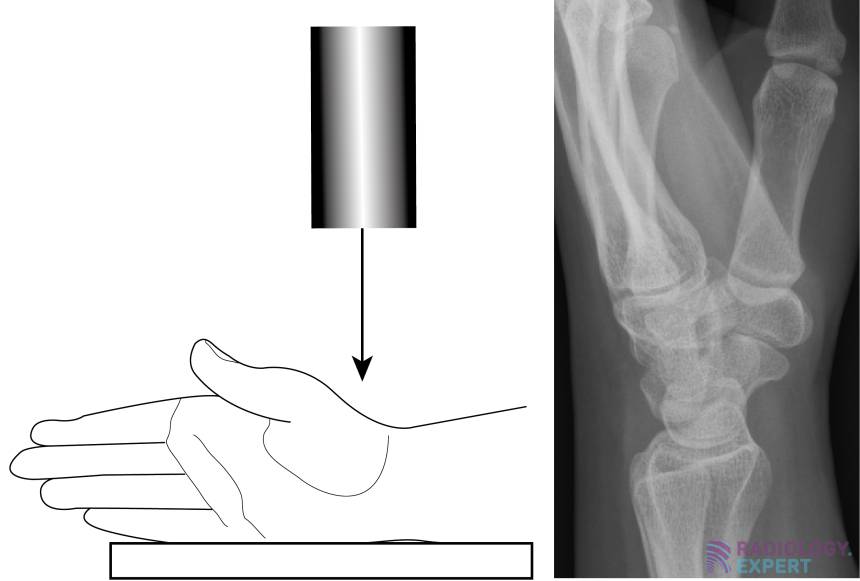

From www.radiology.expert

XWrist X Wrist Instructions High blood pressure can cause stroke, heart attack and dementia, to name a few. Please read the user manual for clear instructions on how to accurately measure your bp. X Wrist Instructions.